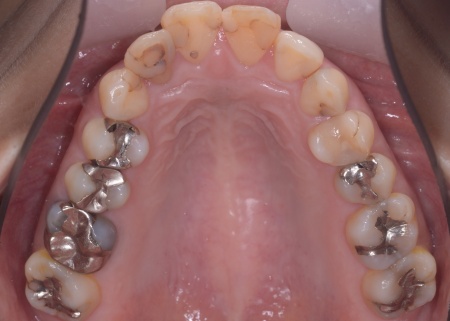

30代女性 出っ歯と開咬に対しアンカースクリューを用いたワイヤー矯正で治療した症例

拝見したところ、上前歯が大きく前に出ている上顎前突であり、上下の前歯が噛み合わずに口を閉じても前歯同士が接触しない「開咬(かいこう)」の状態でした。

レントゲン撮影をして詳しく調べた結果、歯の位置だけでなく、骨格的な問題があることが分かりました。

また、前歯で食べ物をうまく噛み切ることができないため、奥歯にも強い負担がかかっているだけでなく、このまま放置すると、奥歯がすり減ったり痛みが生じたりするリスクもあります。

患者様の場合、骨格的な上顎前突が噛み合わせを乱している主な原因であることから、矯正治療では前歯を後方へ大きく動かすためのスペースを確保する必要があります。